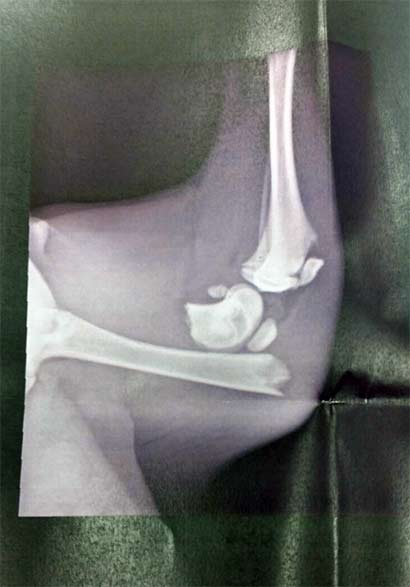

Umgehend wurde ein Termin beim Tierarzt zum Röntgen vereinbart und da sah man dann die sehr traurige Wahrheit:

Miras Hinterfuss ist dreifach gebrochen.

In der Spezialklinik wurde festgestellt, dass die tapfere Maus schon lange diese unheimlichen Schmerzen ertragen musste. Ihre Muskulatur war durch die länger zurückliegenden Brüche bereits verkürzt und dadurch das Bein schon nach Innen gedreht. Mira wurde sofort operiert, dass sie endlich keine Schmerzen mehr ertragen muß! Außerdem zählte jeder Tag, da die junge Hündin schließlich mitten im Wachstum steckt und schnellstens wieder lernen muß, dass sie ihr verletztes Bein tatsächlich auch benutzen kann.